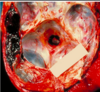

What is the name for this basal skull fracture sign? [1]

Hemotympanum